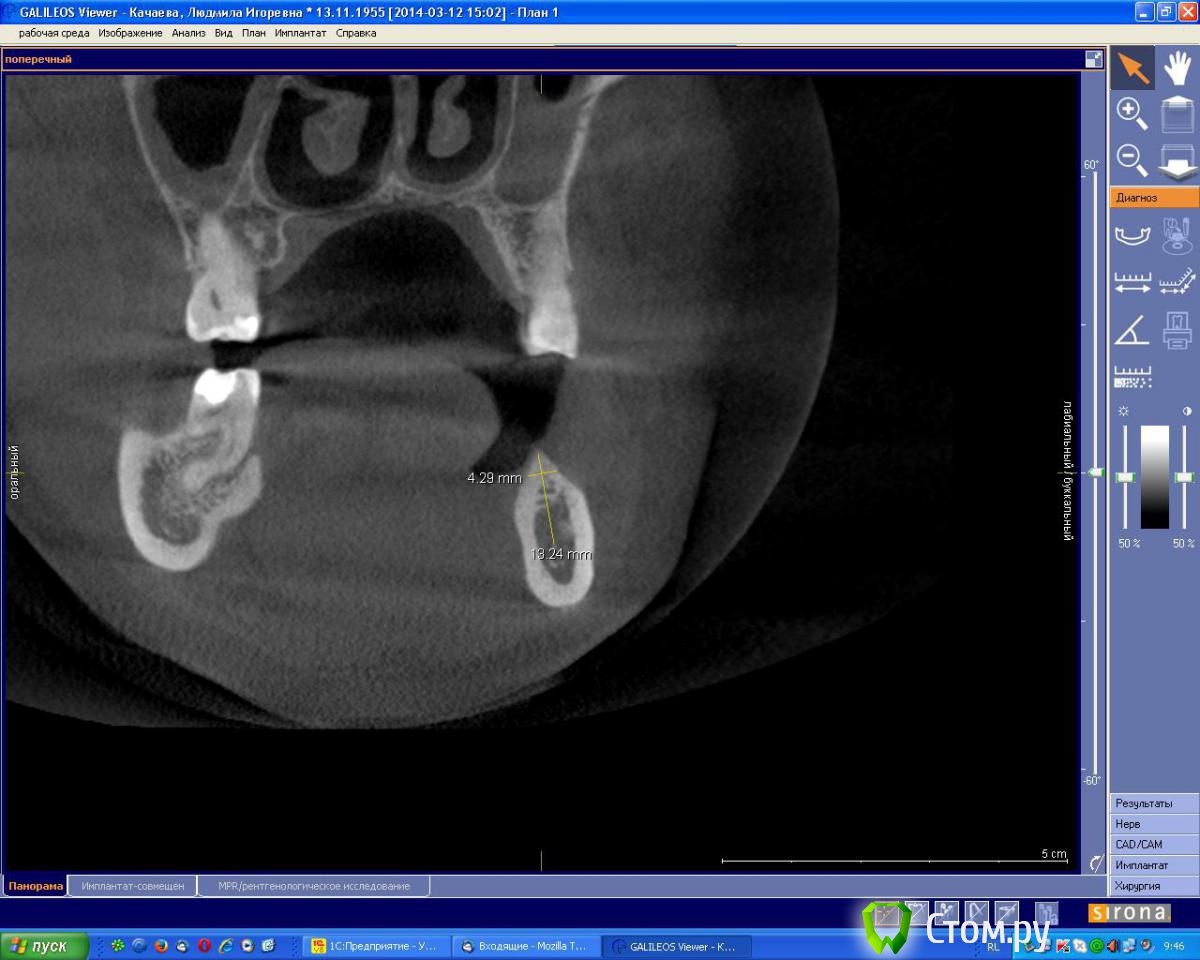

an_ver Опубликовано 7 августа, 2014 Поделиться Опубликовано 7 августа, 2014 Планируется установка 2 имплантов в обл.35,37 по высоте проходит,по толщине нет.Предпочтительный метод в данной ситуации? Ссылка на комментарий

Аслан Опубликовано 7 августа, 2014 Поделиться Опубликовано 7 августа, 2014 (изменено) Вот тут бы без сомнений просто поставил чуть поглубже и вестибулярно досыпал.Хотя можно и заморочиться и перевернуть блок, как показывал Эдуард. Изменено 7 августа, 2014 пользователем Аслан 4 Ссылка на комментарий

Mane Опубликовано 7 августа, 2014 Поделиться Опубликовано 7 августа, 2014 Задача - поставить болт так что по кругу своя кость получилась - или просто зуглибив или расщепление и перевернутый блок. Далее сразу НКРВозможно сразу с десной 2 Ссылка на комментарий

an_ver Опубликовано 8 августа, 2014 Автор Поделиться Опубликовано 8 августа, 2014 Задача - поставить болт так что по кругу своя кость получилась - или просто зуглибив или расщепление и перевернутый блок. Далее сразу НКРВозможно сразу с деснойСделал как вы рекомендовали.Поставил 3,7*10 мм ниже уровня язычной стенки на 1 мм, наскреб с наружной СейСкрепером 0,5 кости,смешал с ГенОсс плотненько утрамбовал и мембрана Эволюшен.Вестибулярно мобилизовал как вы показали (оч.понравилось) язычно слегда распатором растянул,ушился совсем без натяга)). Спасибо за рекомендации 1 Ссылка на комментарий